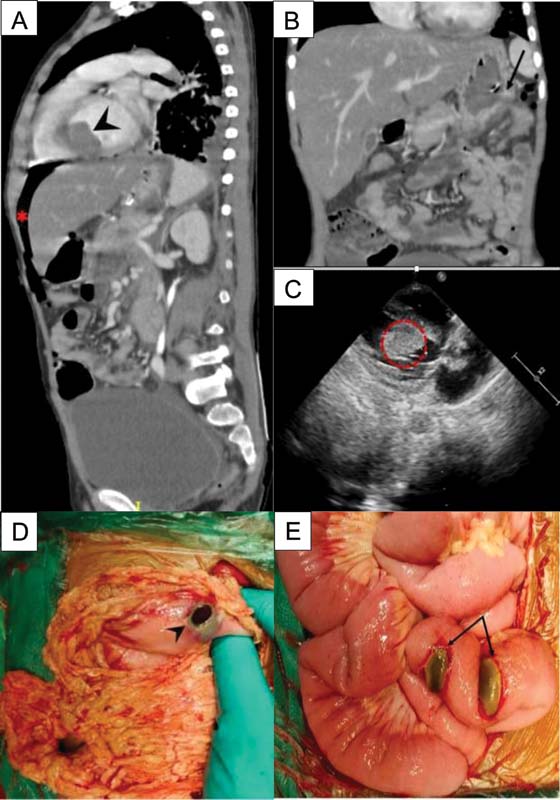

An 8-year-old male presented with on and off fever, bruising over shin and chest and easy fatigability for 2 weeks. A complete blood count showed a total leukocyte count (TLC) of 153???109?/L with a differential count of 60% lymphocytes, 3% neutrophils, 0.1% eosinophils, and 27% blasts in the peripheral blood. A bone marrow examination was done, flow cytometric analysis along with FISH study which was positive for t(9;22), confirmed the diagnosis of B-lineage Ph+?ALL. A real-time quantitative polymerase chain reaction (RT-PCR) was suggestive of p190 BCR/ABL fusion transcript. Cerebrospinal fluid analysis was uninvolved for disease. He was treated as per the modified COG AALL1131 protocol. Induction chemotherapy consisted of prednisolone (60?mg/m2/day; 1?28 days), vincristine (1.5?mg/m2/d; days 1, 8, 15, and 22), native?Escherichia coli?L-asparaginase (10,000 U/m2/d; days 1,4, 7, 10, 13, 16, 19, and 22) daunorubicin (30?mg/m2/d; days 1 and 15), intrathecal methotrexate (12?mg; days 1, 8, and 30) along with daily imatinib (340?mg/m2/once daily) from day 10. Chemotherapy was administered through peripheral intravenous lines on an outpatient basis. Treatment was uneventful up to day 29 of induction when he presented with abdominal pain and fever. On examination, heart rate was 86/min, blood pressure was 100/70?mm Hg and respiration was 22/min. Abdomen was mildly distended, diffusely tender, and bowel sounds were present. He was started on intravenous fluids, intravenous antibiotics (cefoperazone-sulbactam and amikacin), and analgesics for abdominal pain. The complete blood count showed a hemoglobin of 5?g/dL, platelet of 49???109/L, and TLC of 0.42???109/L with an absolute neutrophil count of 0.1???109/L. Blood tests showed an elevated lipase (1,164 U/L), elevated D-dimer (3,700?ng/mL), with a normal serum sodium (137?mEq/L) and potassium (4.2?mEql/L) and no organism was isolated from blood culture. In view of the above symptoms in a neutropenic child, computerized tomography (CT) scan of the abdomen with contrast was performed on the day of admission which revealed a bulky pancreas with fat stranding consistent with acute pancreatitis, as well as perforation of the greater curvature of the stomach resulting in pneumoperitoneum ([Fig. 1a] and [b]). An incidental finding on CT scan was a well-defined hypodense mass in the left ventricle (LV) of the heart which an ultrasound study showed lacked vascularity; two-dimensional echocardiography confirmed a mass of 3.01???1.49?cm arising from the interventricular septum with a normal ejection fraction of 60% ([Fig. 1a] and [c]). Imaging findings and elevated D-dimer both strongly suggested a diagnosis of intraventricular thrombus. The child was shifted to the intensive care unit (ICU) where he was continued on analgesics and intravenous antibiotics and kept nil by mouth. He underwent an emergency laparotomy for his abdominal emergency. Intraoperatively, there was a single perforation on the posterior wall of the stomach, and two impending perforations on the proximal jejunal wall, all of which were closed in two layers, using 4-0 polydioxanone suture ([Fig. 1d] and [e]). The surgical procedure was uneventful. Postoperatively, the child continued to be neutropenic (absolute neutrophil count: of 0.1???109/L) with a platelet count of 40???109/L. He was continued on intravenous antibiotics and was started on the low-molecular weight heparin (LMWH) enoxaparin at 1?mg/kg/dose twice a day for the large cardiac thrombus. Given his postoperative state and neutropenia, it was decided to defer any major cardiac surgery. The day after surgery the child was extubated from the ventilator and started on clear liquids, his pancreatic enzymes had returned to normal. On the subsequent day (postoperative day 2) he developed a sudden cardiac arrest and could not be revived. Permission for autopsy was not obtained.

|?Fig. 1(A)CT abdomen showing left ventricular thrombus (arrow head) and pneumoperitoneum (*) (B) with gastric perforation (arrow). (C) 2D-echocardiography confirming the presence of left ventricular thrombus (outlined circle). (D) Intraoperative findings showing perforation of greater curvature of stomach (arrow head) (E) impending perforation of jejunum (double arrow).